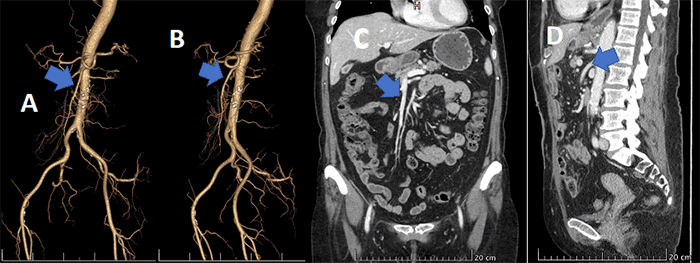

A 70-year-old female with biopsy-proven squamous cell carcinoma (SCC) of the mid-esophagus underwent minimally invasive modified McKeown laparoscopic esophagectomy (MIE)1‒4 (Figure 1A). She had received neoadjuvant chemoradiation prior to surgery.5,6 Preoperative workup included a computed tomographic angiography (CTA) revealing patent mesenteric vessels (Figure 2) and a negative evaluation for metastatic disease (Table 1).

Figure 2. Preoperative CTA of Abdomen and Pelvis (C, D) with 3D Reconstruction (A, B) Revealing Patent Superior Mesenteric Artery (arrow). Published with Permission